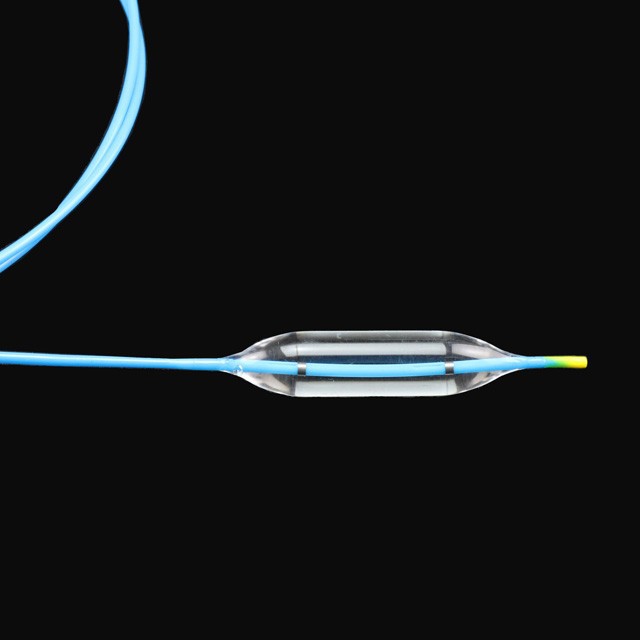

Bul બલૂનને ચોક્કસ દબાણ હેઠળ ત્રણ અલગ વ્યાસ પર સ્નાતક વધારી શકાય છે, ચિકિત્સકો માટે વધુ પસંદગી પૂરી પાડે છે .

● સ્થિતિસ્થાપક સોફ્ટ ટીપ ડિઝાઇન, જે ઓછા નુકસાન સાથે લક્ષ્યની સ્થિતિમાં સરળતાથી પ્રવેશ કરી શકે છે .

● ઝડપી ડ્રેનેજ ડિઝાઇન સર્જરીનો સમય ઘટાડવામાં મદદ કરે છે .

High ઉચ્ચ દબાણ પ્રતિકાર અને સલામત વિક્ષેપ સાથે આયાત કરેલી સામગ્રીનો ઉપયોગ કરો .

Mult મલ્ટિ-વિંગ પ્લેટીંગ પછી થર્મોસ્ટેટિક આકાર કાર્યકારી ચેનલથી ઉત્તમ સ્થિતિસ્થાપકતા અને લવચીક પીછેહઠમાં ફાળો આપે છે .

The ટ્યુબની શ્રેષ્ઠ ડિઝાઇન તેને સરળ અને સારી સ્થિતિસ્થાપકતા, મજબૂત વળી જતું પ્રતિકાર અને સરળ પસારતા બનાવે છે .

The બલૂનના બંને છેડા પર રેડિયોપેક માર્કર્સ એક્સ-રે હેઠળ ચોક્કસ સ્થિતિ પ્રદાન કરી શકે છે .

● પ્રી-ઇનપુટ 0 . 035 "સોફ્ટ ટીપ અને માર્ક સાથે માર્ગદર્શિકા વાયર, જે અંદરના માર્ગદર્શિકા વાયરની લંબાઈનો અંદાજ કા .વા માટે સરળ છે.